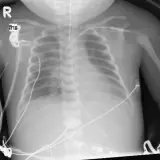

Over 2,100 interactive radiology cases, curated by radiologists for your level of training. Scroll, window, and view cases full screen — just like on PACS. Click linked findings in each writeup to jump straight to them on the image. Cases include sample reports, a focused discussion section, original illustrations, and videos.

Des cas entièrement interactifs avec les outils attendus d'un PACS — défilement, fenêtrage, zoom, déplacement, mesures, ROI et mode plein écran.

Des annotations détaillées mettent en évidence les résultats clés directement sur les cas. Cliquez sur les résultats liés dans les descriptions de cas pour accéder à leur emplacement exact sur l'examen.